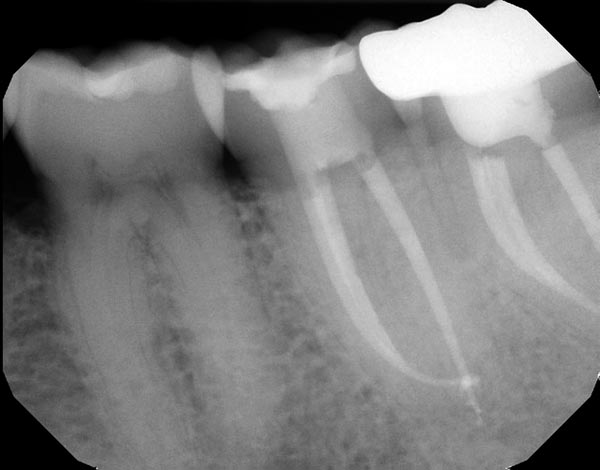

Fig. 5a: Preoperative image of tooth #18 with an irreversible pulpitis and a suspected fracture. The standard anatomy in this tooth could likely be instrumented with a variety of different file systems. Fig. 5b: I used ProTaper Next from Dentsply Sirona to safely and efficiently manage the subtle curve at the mesial root apex. Because of the variable taper built into the file design, only two files were needed to create the final shapes.

Fig. 5a

Fig. 5b